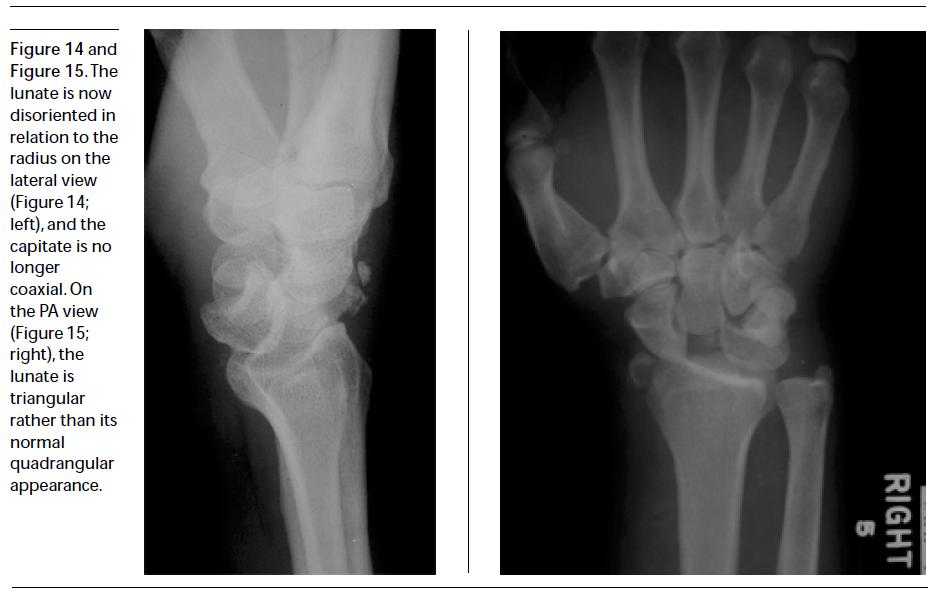

Radiological signs of a true lunate dislocation BMJ Case Reports Fractured Lunate Bone Symptoms The most common symptoms of kienböck's disease include: The disorder prevents the lunate. Diagnosis can be made with. The complaints are in most cases longstanding and increase progressively. Kienbock’s disease is a rare bone disorder that affects the lunate, one of your eight wrist bones. Kienbock's disease is the avascular necrosis of the lunate which can lead to progressive wrist. Fractured Lunate Bone Symptoms.